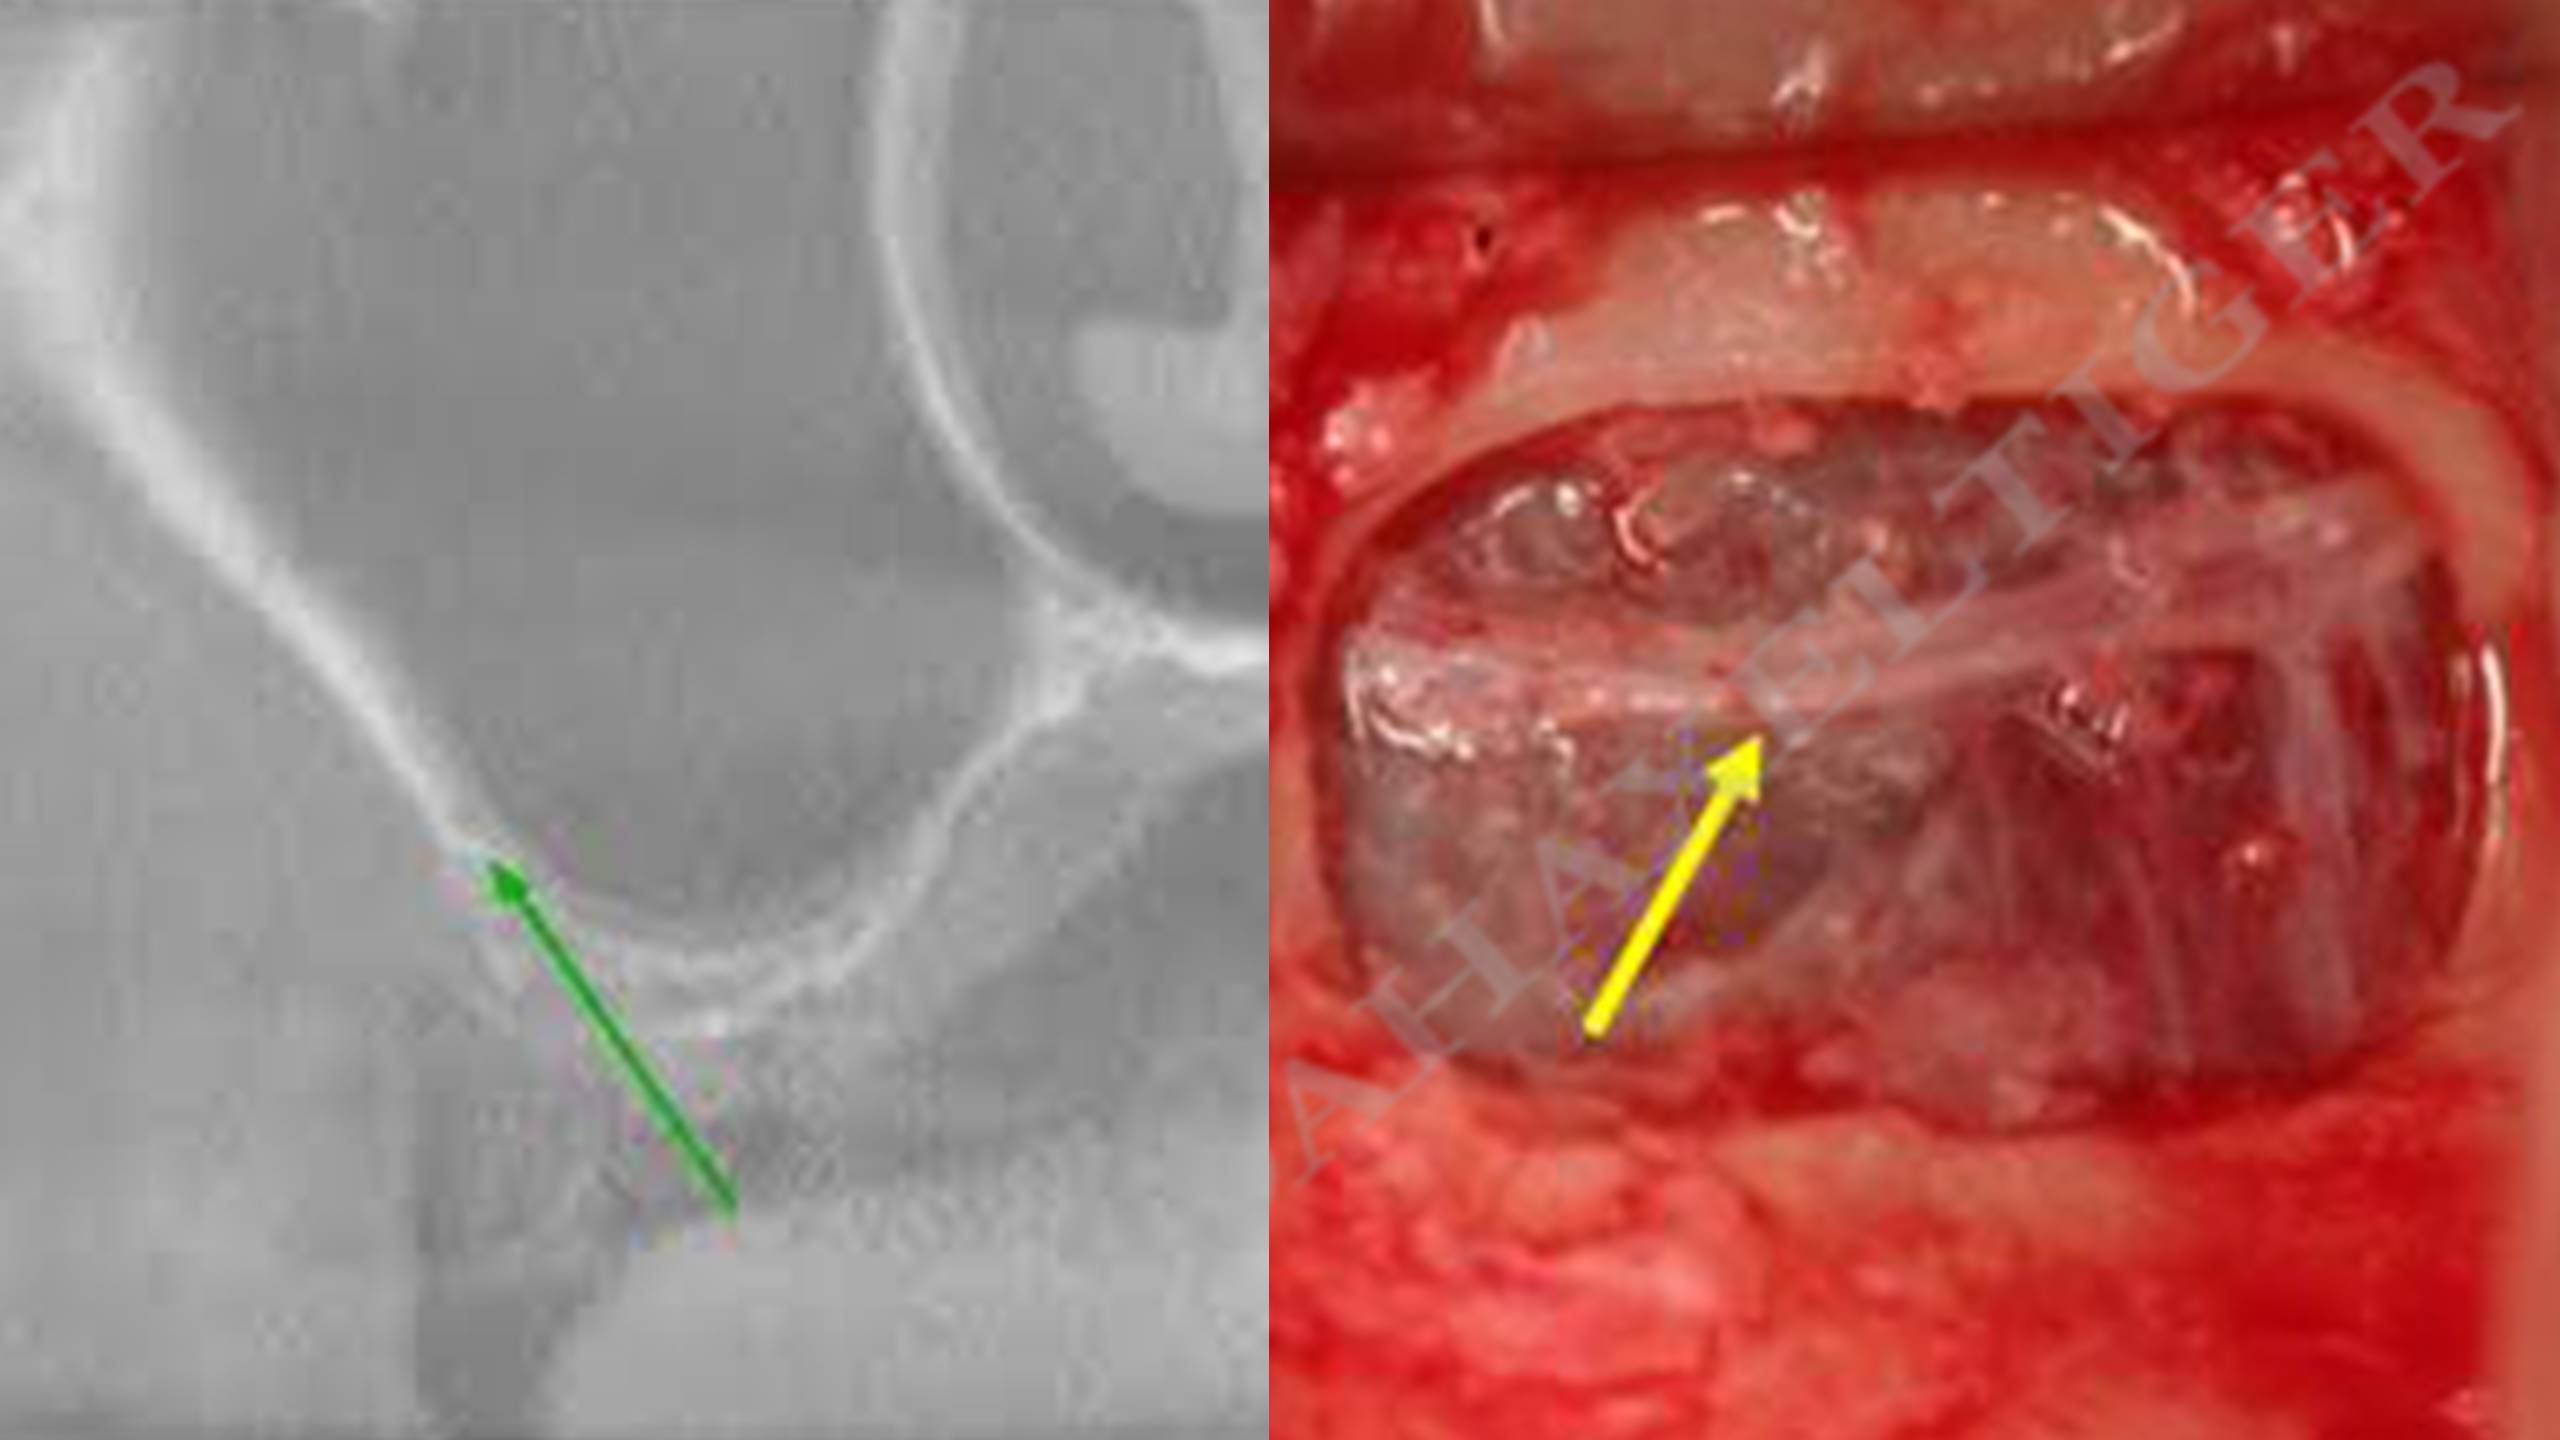

Vue radiologique et in situ de l’artère antrale dont la position va définir la localisation de l’ostéotomie.

Visualisation du matériau avant qu’il ne soit refoulé dans le sinus.